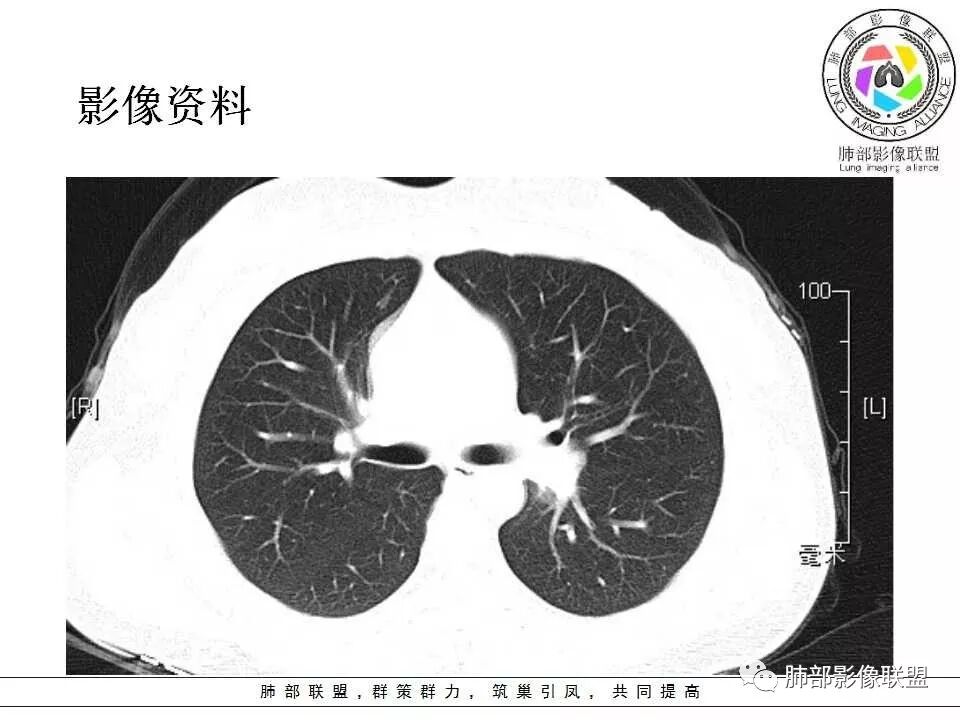

患者中年女性,发现左肺上叶占位,随访发现体积增大。胸部CT:左肺上叶尖后段实性占位,位于支气管旁,未见支气管阻塞,病灶边界清楚,边缘光滑,增强可见病灶均匀强化,血管贴边,考虑良性病变,PSP?

左肺上叶后段紧贴斜裂结节影,支气管通畅,斜裂无移位,说明病灶来源斜裂可能,强化密度均匀,边缘清晰,考虑良性病变,PSP可能性大,鉴别CD。

患者中年女性,发现左肺上叶占位1年余入院,随访发现体积增大。胸部CT:左肺上叶尖后段近肺门及叶间裂实性类圆形结节,病灶边界清楚光滑,增强可见病灶明显均匀强化,其旁未见支气管堵塞。综合考虑良性病变,孤立性纤维瘤可能,鉴别巨大淋巴结增生症及硬化性肺细胞瘤。

青年女性,左肺门占位。定位:跨叶间裂,下叶邻近支气管推压,考虑肺外病变。影像表现:血管贴边,边缘光滑,强化均匀,考虑良性病变,PSP可能大,鉴别CD。

年轻女性,左肺门区占位,斜裂推移未跨叶,类圆形,增强扫描明显强化,和支气管关系显示不是太清楚,感觉关系不是太密切,未见阻塞性炎症,一年后有长大,首先考虑PSP,鉴别类癌,SFT。